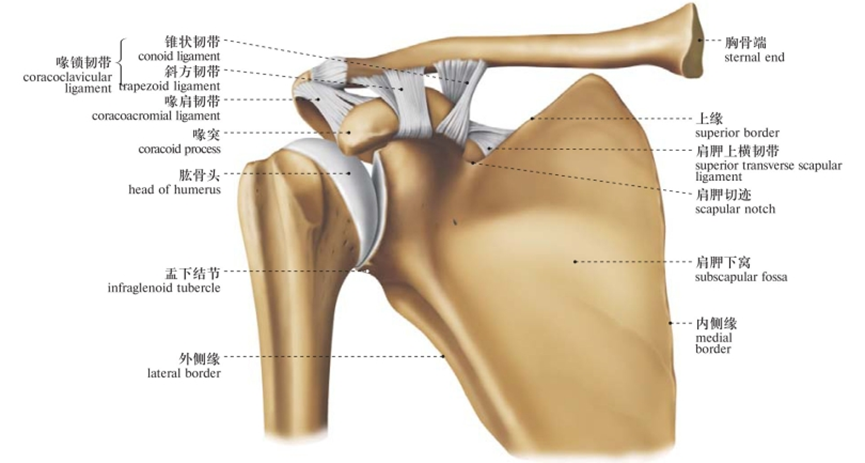

图1/2 肩关节韧带(前面观)

由肩胛骨的关节盂与股骨头组成,又叫肩肱关节(盂肱关节)。是典型的多轴球窝关节,为全身最灵活的关节,可作三轴运动,即冠状轴上的屈和伸,矢状轴上的收和展,垂直轴上的旋内、旋外及环转运动。

因肱骨头较大,呈球形,关节盂浅而小,仅包绕肱骨头的1/3,关节囊薄而松弛,所以是人体运动范围最大而又最灵活的关节。

这个结构上的特点虽然保证了它的灵活性,但它的牢固稳定性都较其他关节为差,是全身大关节中结构最不稳定的关节。

囊外:喙肱韧带、喙肩韧带及肌腱加强其稳定性。

1.喙肱韧带:

自喙突至肱骨大结节,部分纤维在后上部与关节囊融合,增强关节囊上部,防止肱骨头向上脱位。

2.盂肱韧带:

位于关节囊前壁,可分为上、中、下三部,自关节盂周缘前部至肱骨小结节。有加强关节囊前壁的作用。

3.肱骨横韧带:

为肱骨的固有韧带,横跨结节间沟的上方,有固定肱二头肌长头腱于结节间沟的作用。